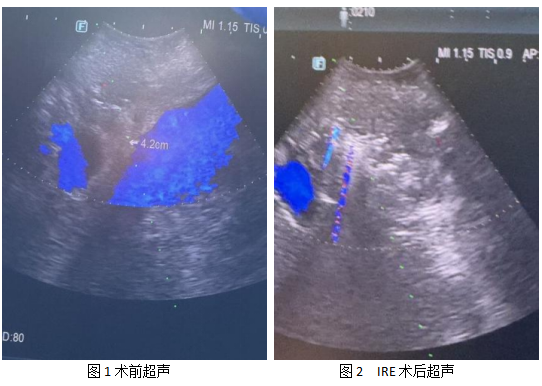

面对患者的病情与家属的期盼,在谭刚主任的指导与支持下,翟博教授团队第一时间开展多学科会诊,对患者的肿瘤位置、血管侵犯程度、身体耐受情况进行全面、精准评估,最终制定了联合不可逆电穿孔(IRE)的个体化治疗方案。在麻醉科、超声科、手术室的紧密协作下,团队凭借精准的操作,顺利完成消融治疗,手术过程平稳顺利,有效保护了肿瘤周围血管、胆管等重要组织,实现了对肿瘤的精准灭活。

术后,在普外二病房医护团队的精心护理下,张阿姨恢复顺利,腹痛、黄疸症状明显缓解,各项指标逐步改善,现已顺利进入康复阶段。